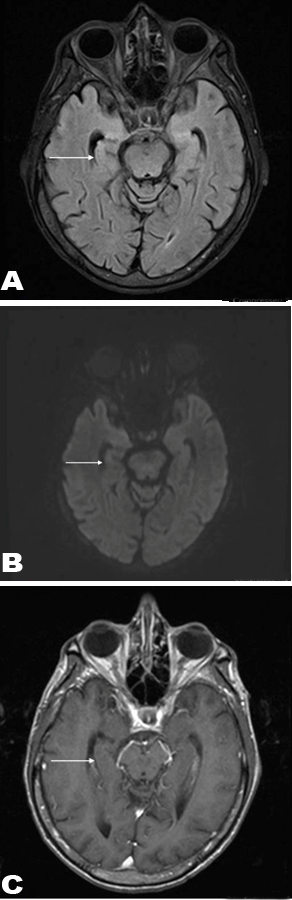

A 56-year-old male with recently diagnosed rectal cancer presented in the emergency department with recurrent seizures and disorientation for some days. Magnetic resonance imaging scan of brain demonstrated hyperintense signal on T2- FLAIR image (Figure 1A) and restricted diffusion on diffusion weighted image (Figure 1B) in right medial temporal lobe. There was no enhancement after contrast administration (Figure 1C). Patient's initial computed tomography (CT) scan of the abdomen and pelvis (Figure 2A-B), and positron emission tomography (PET) scan (Figure 2C) showed the presence of a large rectal mass with intense metabolic uptake. Based on clinical history and imaging findings, diagnosis of PLE was suggested. Serologic investigation showed a highly positive titer for anti-Ri (1:2560, normal <80). Subsequent cerebrospinal fluid analysis also showed increased titers of anti-Ri antibody with no findings to suggest viral or bacterial encephalitis. Since patient was already on chemotherapy treatment for rectal cancer, antiepileptic therapy and steroid treatment were also started. In next few days, the patient was free from seizure episodes and the neurological symptoms gradually improved. Follow-up MRI scan of brain was showed complete interval resolution of the abnormalities (Figure 3A-C).

Figure 1: (A) Axial T2-FLAIR image demonstrating abnormal hyperintense signal in right medial temporal lobe, (B) Diffusion weighted image showing restricted diffusion in right medial temporal lobe, and (C) Contrast enhanced axial T1-weighted image showing lack of contrast enhancement.

Paraneoplastic neurologic syndromes are a group of neurologic disorders associated with malignancy affecting any part of the nervous system and include PLE, subacute cerebellar degeneration and sensory neuropathy [1]. Paraneoplastic limbic encephalitis one of the paraneoplastic neurologic syndromes, is caused by autoimmune-related inflammatory process localized to the limbic system. It is characterized by slowly progressive behavioral changes, memory loss, seizures and cognitive dysfunction [1]. Small cell lung cancer is most frequent associated malignancy. Other associated cancers include testicular tumors, breast cancer and Hodgkin lymphoma [2]. Infrequently, colon and rectal adenocarcinoma have also been shown to be associated with PLE. The most frequent antibodies are anti-Hu and anti-Ma2 antibodies which can be detected in serum and CSF, thus aiding in diagnosis [2]. Anti-Ri antibody is particularly associated with colon and rectal cancers [2]. As in any other intracranial abnormalities [3] [4], MRI scan is the imaging modality of choice. A brain MRI scan is helpful by demonstrating characteristic MRI finding of high signal intensity in bilateral or unilateral medial temporal lobes on T2-Flair images with mild restricted diffusion. Since DW images show restricted diffusion in the abnormal areas with cytotoxic edema and high cellularity [5] [6], PLE will also show restricted diffusion in most of the cases [7]. MRI scan also helps in excluding other pathologies with similar neurologic symptoms [8]. Differential diagnosis of MRI findings includes herpes encephalitis and low grade glioma. However, herpes encephalitis will usually involve the entire temporal lobe with involvement of the frontal lobe, with presence of hemorrhage in some cases. Low grade gliomas will be unilateral and usually not limited to medial temporal lobe [9]. In difficult cases, history of primary malignancy, serum and cerebrospinal fluid analysis help in making the correct diagnosis.